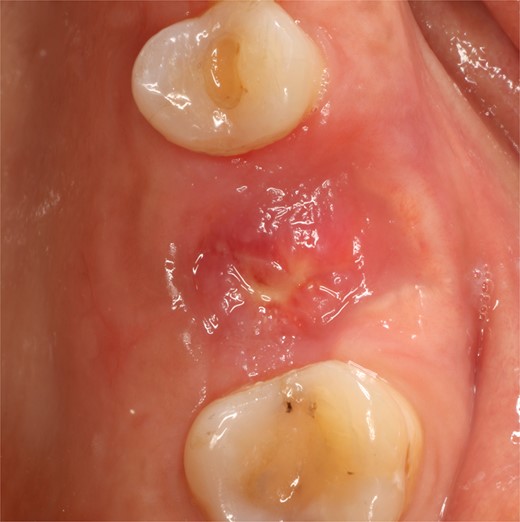

A control appointment was made 8 days later, and the scar tissue with slight erythema on the edges of the alveolus was observed (Fig. 6). The patient was asymptomatic, and the membrane was in position to cover the entire alveolus. After the fourth week, granulation tissue was observed covering almost the entire alveolus, and an area was observed where the membrane found below this granulation tissue could be seen (Fig. 7). About 3 months after surgery, healed soft tissue was observed, and a CT scan was requested, where the maxillary sinus was observed without evidence of pathologies and hypodense alveolar bone compatible with immature bone in the process of calcification (Fig. 8). After 6 months, keratinized tissue and a completely healed alveolus were observed (Fig. 9), and cone beam computed tomography (CBCT) was requested to evaluate the results and see the possibility of placing an implant. In the CT scan, continuous sinus and alveolar cortex were observed with an image compatible with bone in the healing process (Fig. 10).